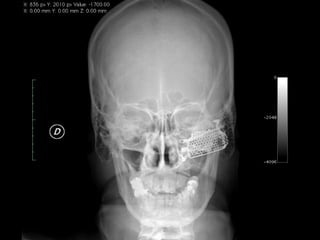

Implantes de titanio en cara

Implantes de titanioen cara Consideraciones generales en implantología